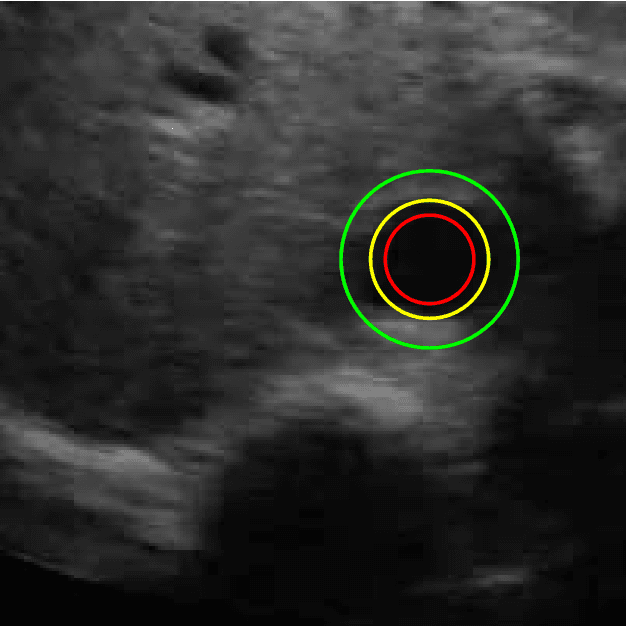

Abstract:Detection of relative changes in circulating blood volume is important to guide resuscitation and manage a variety of medical conditions including sepsis, trauma, dialysis and congestive heart failure. Recent studies have shown that estimates of circulating blood volume can be obtained from the cross-sectional area (CSA) of the internal jugular vein (IJV) from ultrasound images. However, accurate segmentation and tracking of the IJV in ultrasound imaging is a challenging task and is significantly influenced by a number of parameters such as the image quality, shape, and temporal variation. In this paper, we propose a novel adaptive polar active contour (Ad-PAC) algorithm for the segmentation and tracking of the IJV in ultrasound videos. In the proposed algorithm, the parameters of the Ad-PAC algorithm are adapted based on the results of segmentation in previous frames. The Ad-PAC algorithm is applied to 65 ultrasound videos captured from 13 healthy subjects, with each video containing 450 frames. The results show that spatial and temporal adaptation of the energy function significantly improves segmentation performance when compared to current state-of-the-art active contour algorithms.